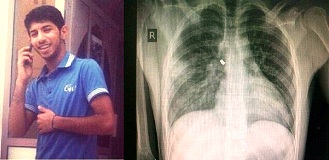

(Ahlul Bayt News Agency) - On 22 Feb 2013, Sayed Majed Sayed Hasan (18 years old) and another boy were shot with bullets by a person driving in a civilian car in Buri, where a pro-democracy protest was taking place. The two boys sustained injuries in the chest and they were taken immediately to the hospital. Sayed Majed underwent a surgery that stabilized his situation, but the bullet remained in his chest. He stayed in hospital until 2 March 2013. He has scheduled surgery on Sunday 28 April to remove the bullet from his chest. While in the hospital, Sayed Majed was interrogated by the police, but no action was taken against the person responsible for the shooting despite the available information that would lead to his identity. According to witnesses, the shooter was driving a black Range Rover car with a license plate containing three digits; witnesses recorded the license plate number. However, license plates with only three digits are normally assigned to "VIP" persons by the government.At dawn on 25 Apr 2013, security forces stormed the home of Sayed Majed and arrested him without presenting an arrest warrant after searching and damaging much of the private property in the home. His family told the BCHR that Sayed Majed informed them via a short call that he was forced to stand for long hours at the criminal investigation department, and whenever he became tired and sat down, he was beaten. He was then taken to the public prosecution where he was interrogated in the absence of a lawyer and was charged with “illegal gathering, rioting, and assault of policemen”. The public prosecution issued an order for Sayed Majed to be kept in detention for 45 days pending investigation. He is currently detained at the Dry dock detention center according to a brief call he made to his family.The Bahrain Center for Human Rights believes that the act of arresting a victim of an attempted murder while the responsible person for the crime is allowed to go free, despite having information that lead to his identity, only confirms growing culture of impunity in Bahrain which continues to leave much of the population without any protection of the law.In addition, the Bahrain Center for Human rights expresses concern for the life and safety of Sayed Majed, who still has a bullet lodged in his chest and who needs to have access to proper medical treatment.The Bahrain Center for Human Rights calls for the following:- Immediately release Sayed Majed and provide him with the complete medical treatment required for his rehabilitation.- Launch an investigation and bring the responsible party of the shooting of the two boys to justice, and hold him/her accountable for the attempted murder.- Put an end to the culture of impunity and bring those accountable for the protection of criminals to justice including the officials at the public prosecution./129

Bahraini authorities took to arrest and prosecute a shooting victim before he completed full medical treatment, while at the same time the shooter was not held accountable for his crime.